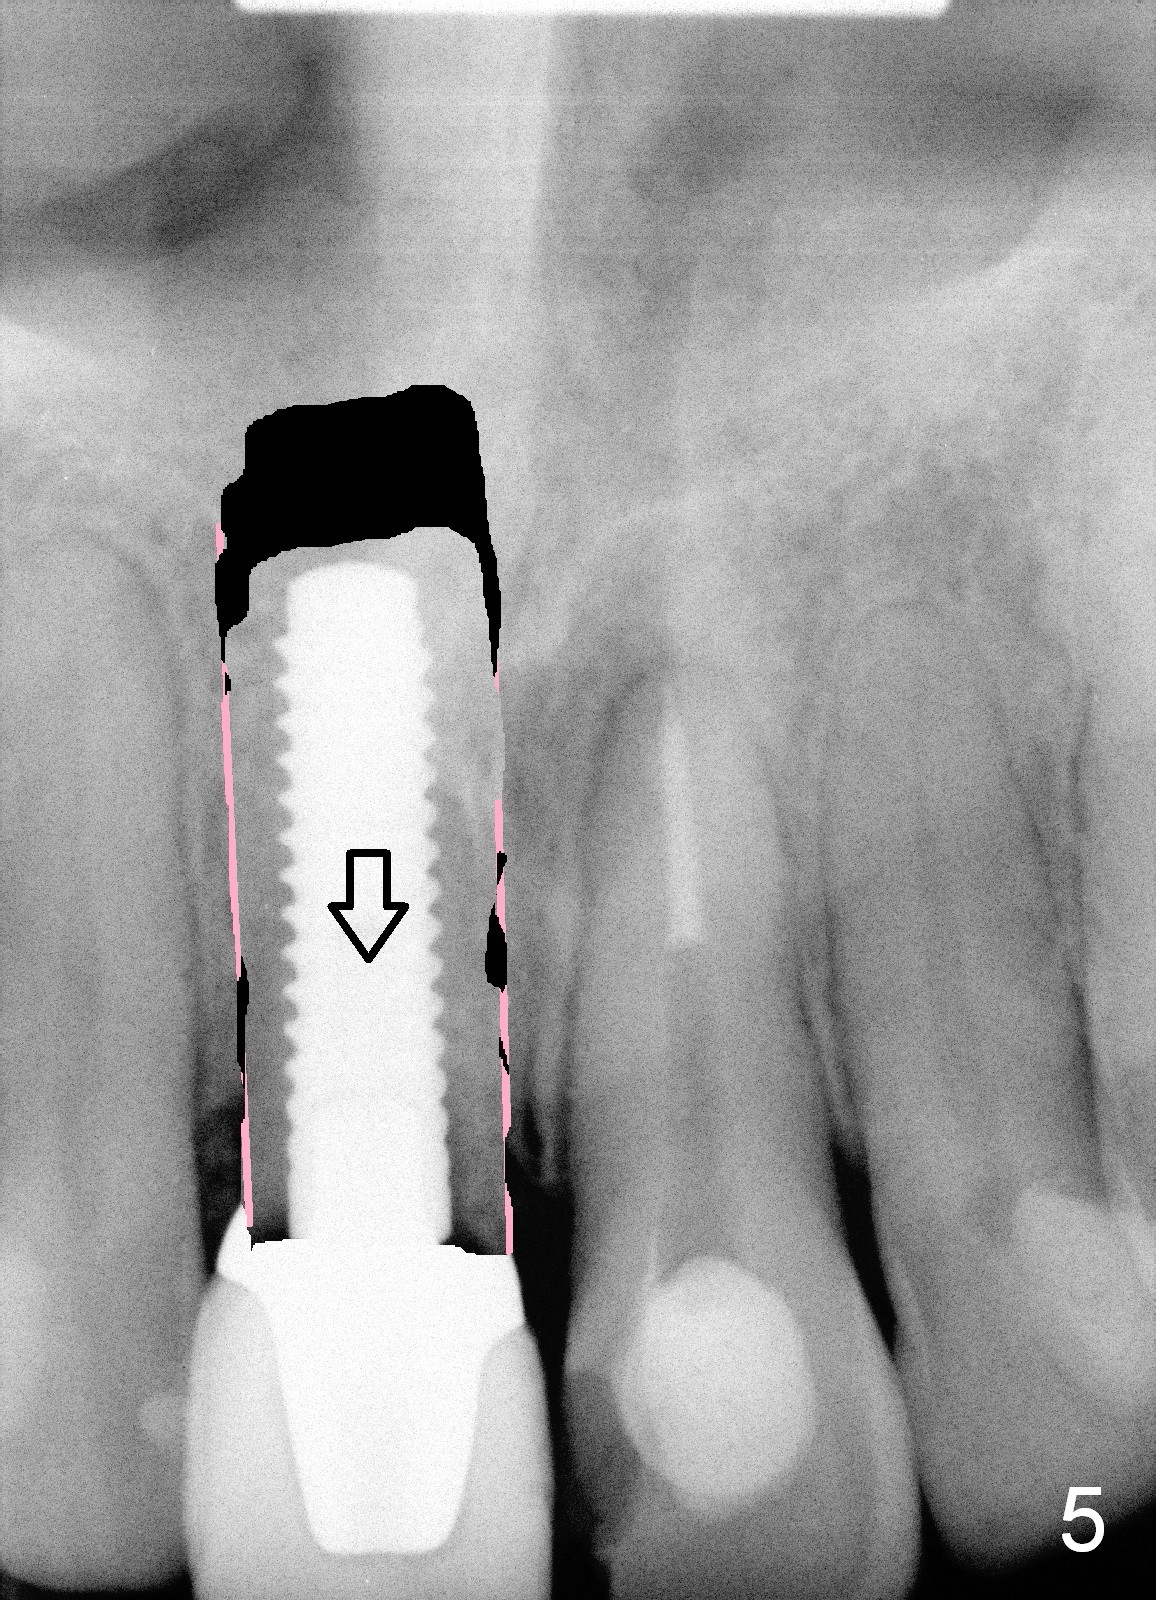

Immediate implant allows an anterior implant to be placed away from the nasal floor (Fig.1 arrowheads). In case the implant needs to be repositioned after osteointegration, there is room for a transverse cut (red line: vertical cut: pink). When the implant bony segment moves coronally (Fig.2 arrow), a block graft is inserted in the apical space (yellow) to prevent relapse.